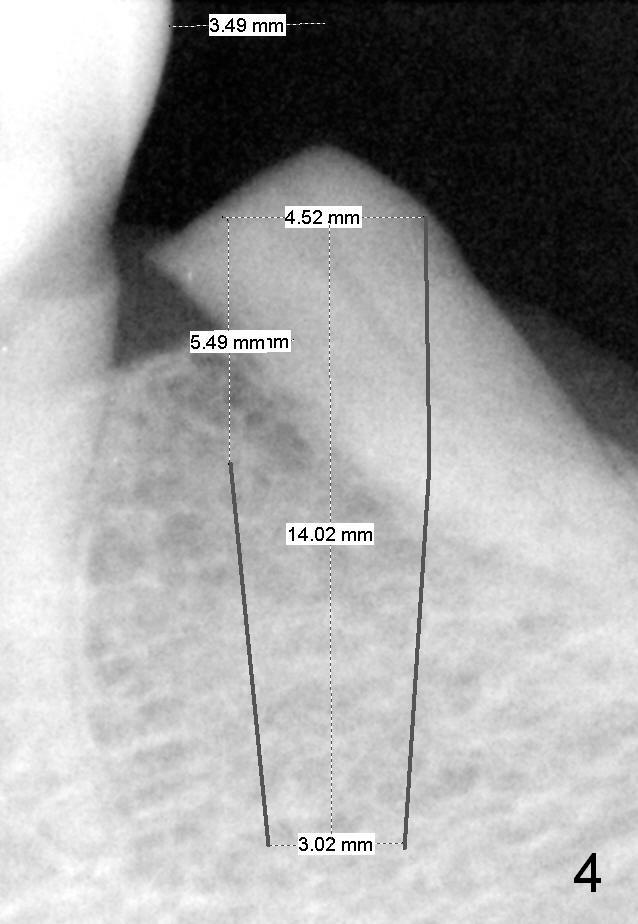

A 78-year-old lady is scared of dentistry, but she has no problem having a 2nd immediate implant (#20 in Fig.1) once the 1st one turns out to be without pain. The challenge associated with #20 is its long axis. After extraction, the osteotomy is initiated in the mesial socket wall at the junction of the upper and middle 1/3 obliquely (Fig.2, slightly lingually). Once the entry is obtained, the axis of the pilot drill is changed to be parallel to the neighboring tooth (Fig.3); an implant spacer of 2.5 mm is used to check (against the 2 mm pilot drill) so that the center of the osteotomy is 3.5 mm from the neighboring tooth (Fig.4). The implant will be 4.5x14 mm. The depth is not longer than that of the neighboring tooth so that it should be quite safe relative to the Mental Loop and the Inferior Alveolar Canal (yellow dashed line in Fig.1). The apical socket is packed with collagen dressing while the coronal one with bone graft. An immediate provisional will be fabricated to keep the graft in place. The osteotomy should be as lingual as possible to avoid the Mental Loop (Fig.1' red dashed line).